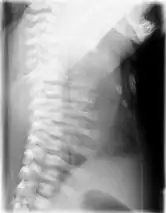

Lateral CXR of the same person above

Jeune syndrome is a rare genetic disorder that affects the way a child’s cartilage and bones develop. It begins before the child is born and primarily affects the child's rib cage, pelvis, arms and legs.[5] Usually, problems with the rib cage cause the most serious health problems for children with Jeune syndrome. Their rib cages (thorax) are smaller and narrower than usual, which inhibits the child's lungs from developing fully or expanding when they inhale. The child may breathe rapidly and shallowly. They may have trouble breathing when they have an upper or lower respiratory infection, like pneumonia. Breathing trouble can range from mild to severe. In some children, it is not noticeable, aside from fast breathing; however, in others, breathing problems can be fatal. About 60% to 70% of children with this condition die from respiratory failure as babies or young children. Children with Jeune syndrome who survive often develop problems with their kidneys, and over time they may experience kidney failure.[2] As a result, few children with Jeune syndrome live into their teen years. Children with Jeune syndrome have a form of dwarfism. They are short in stature, and their arms and legs are shorter than most people’s.[6]